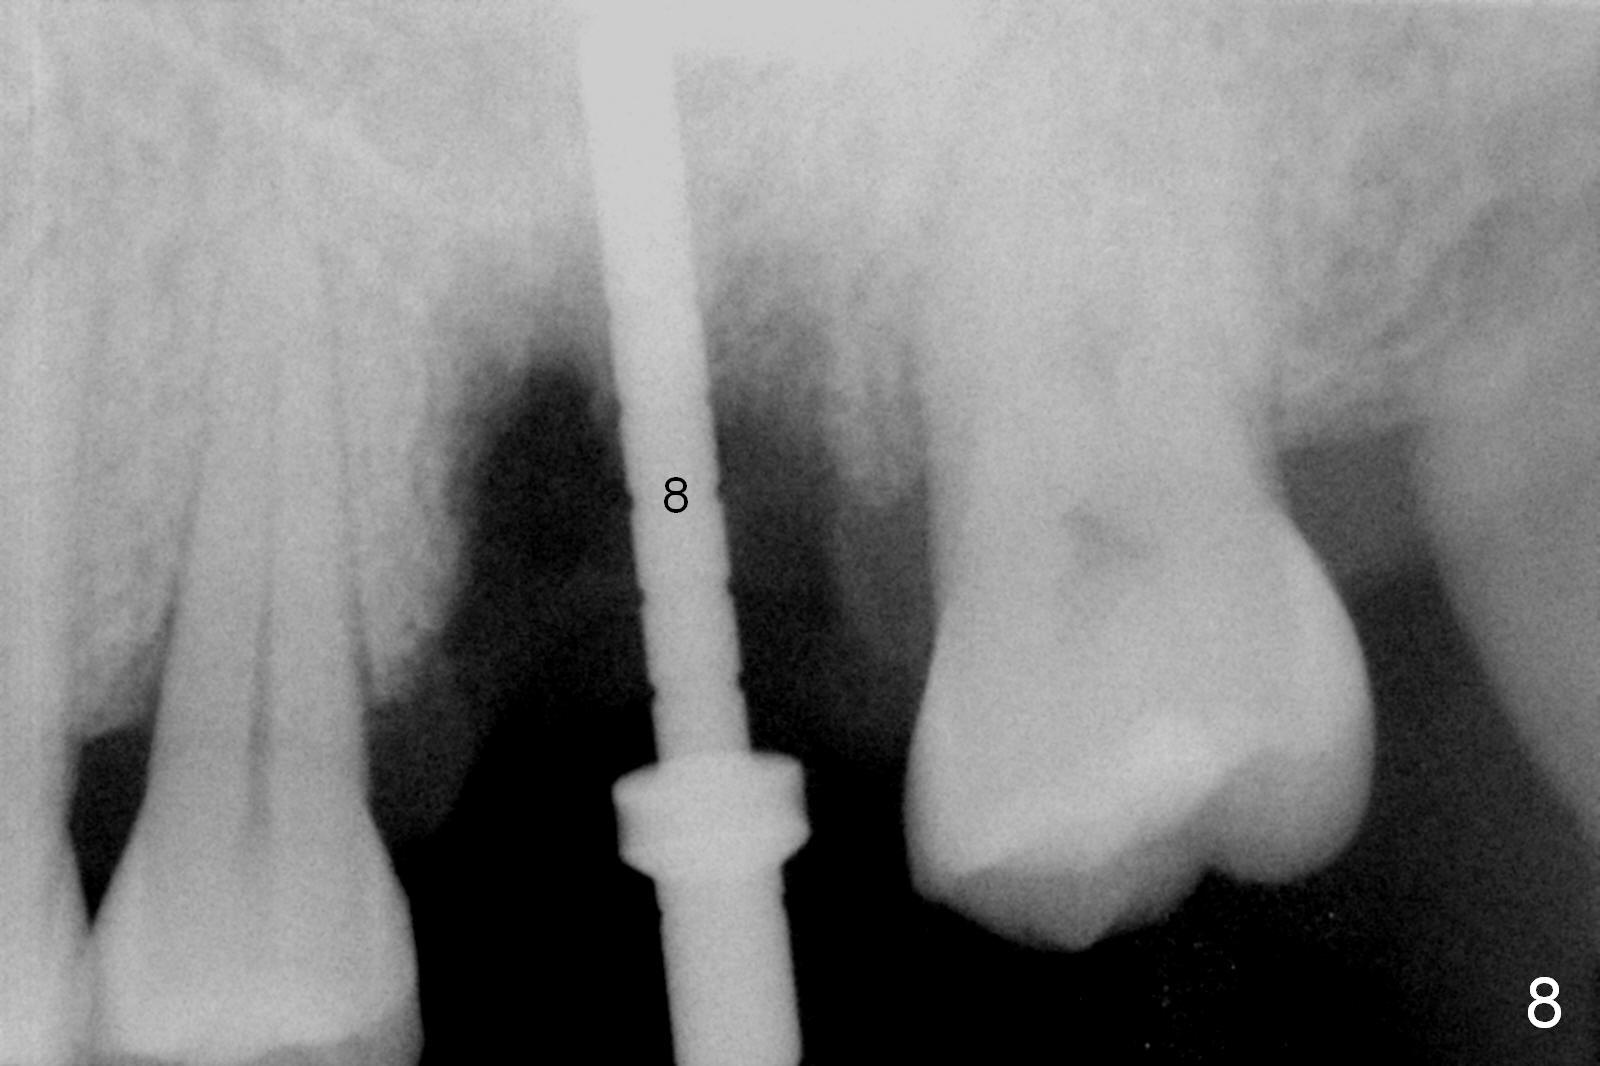

Osteotomy is initiated in the palatal slope of the septum 8 mm deep (Fig.8,9). A 5x11.5 mm implant is placed with insertion torque of 35 Ncm with ~ 2 mm sticking into the sinus with bone graft and 1.5-2.5 mm outside the septum. The latter is covered by bone graft (Fig.10 *). There is no nasal hemorrhage postop.